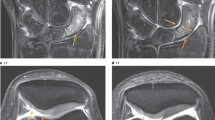

Spatially resolved quantitative T1, T2, T1ρ and T2* maps were obtained for all osteochondral samples. Qualitatively, samples were relatively homogeneous, while uniform changes in signal intensities were found as a function of tissue depth (Fig. 1). Whenever present, focal signal alterations were only slight, and, in any case, adjacent cartilage areas were not affected.

T1 (a), T1ρ (b), T2 (d) and T2* (e) maps of a representative histologically intact cartilage sample. Corresponding morphological images were used for the parameter map overlays. Histological evaluation in terms of Hematoxylin and eosin (c) as well as Safranin O staining (f) revealed no substantial structural or compositional tissue alterations. Units of scale bars are ms.